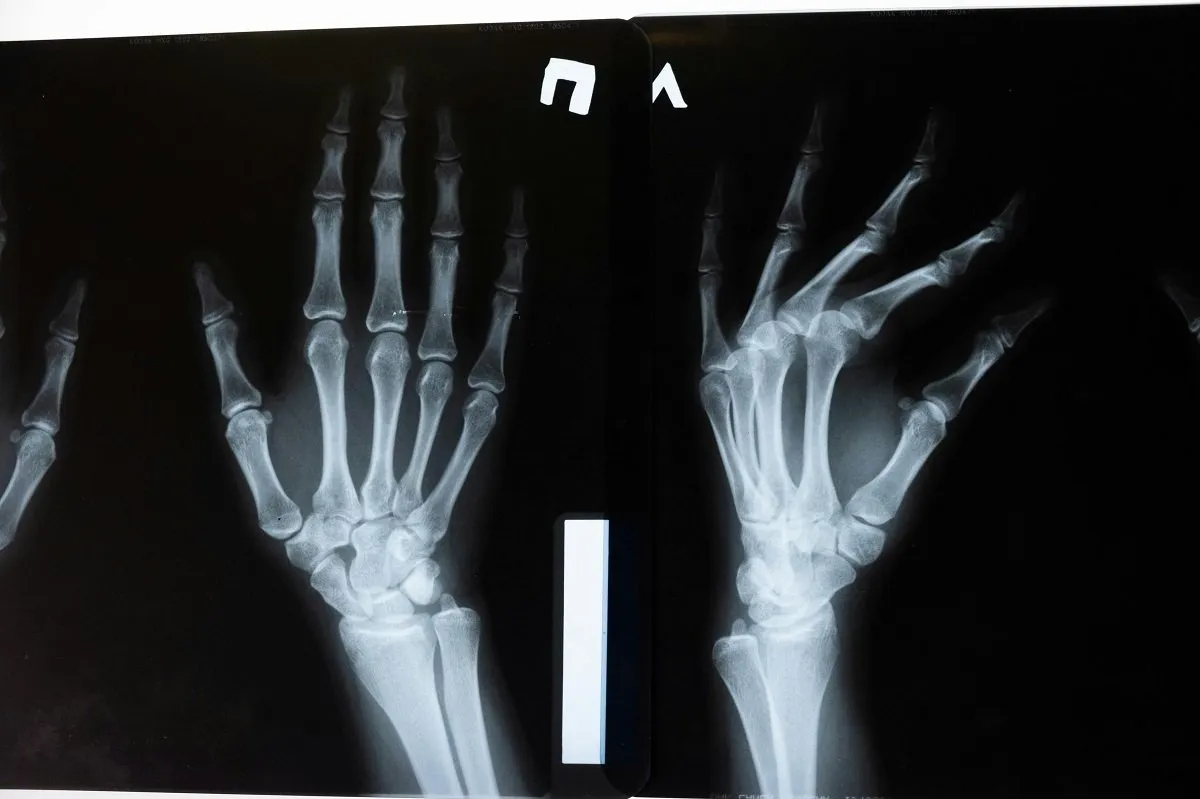

મેડિકલ સાયન્સના ક્ષેત્રમાં એક મોટી સિદ્ધિ હાંસલ થઈ છે. ચીનના સંશોધકોએ એક એવો ખાસ મેડિકલ એડહેસિવ વિકસાવ્યો છે જે તૂટેલા હાડકાં અને ફ્રેક્ચરને માત્ર ત્રણ મિનિટમાં જ જોડી શકે છે. ઓર્થોપેડિક સારવારમાં આ એક મોટી ક્રાંતિ લાવી શકે છે.

“બોન-૦૨” નામનો આ અનોખો ગુંદર ૧૦ સપ્ટેમ્બરના રોજ ઝેજિયાંગ પ્રાંતની એક સંશોધન ટીમ દ્વારા રજૂ કરવામાં આવ્યો હતો. આ પ્રોજેક્ટના નેતા, સર રન રન શો હોસ્પિટલના ઓર્થોપેડિક સર્જન લિન ઝિયાનફેંગે જણાવ્યું કે તેમને આ ગુંદર બનાવવાની પ્રેરણા સમુદ્રમાં જોવા મળતા છીપલાંમાંથી મળી હતી. તેમણે જોયું કે પાણીની અંદર પુલના પાયા પર છીપ કેવી રીતે મજબૂતીથી ચોંટી રહે છે. આમાંથી પ્રેરણા લઈને તેમણે એક એવું એડહેસિવ બનાવ્યું જે લોહીવાળા વાતાવરણમાં પણ માત્ર બેથી ત્રણ મિનિટમાં હાડકાંને મજબૂત રીતે જોડી શકે છે, જ્યાં પરંપરાગત એડહેસિવ કામ કરતા નથી.

આ ‘હાડકાનો ગુંદર’ મેટલ ઇમ્પ્લાન્ટથી સાવ અલગ છે. સામાન્ય રીતે, હાડકાં જોડવા માટે સ્ટીલ પ્લેટ કે સ્ક્રૂનો ઉપયોગ થાય છે, જેને પછીથી બીજી સર્જરી દ્વારા કાઢવા પડે છે. પરંતુ, “બોન-૦૨” કુદરતી રીતે શરીર દ્વારા શોષાઈ જાય છે, જેના કારણે બીજી સર્જરીની જરૂર રહેતી નથી. આનાથી દર્દીને થતી પીડા અને શસ્ત્રક્રિયાનો ખર્ચ બંનેમાં ઘટાડો થશે.